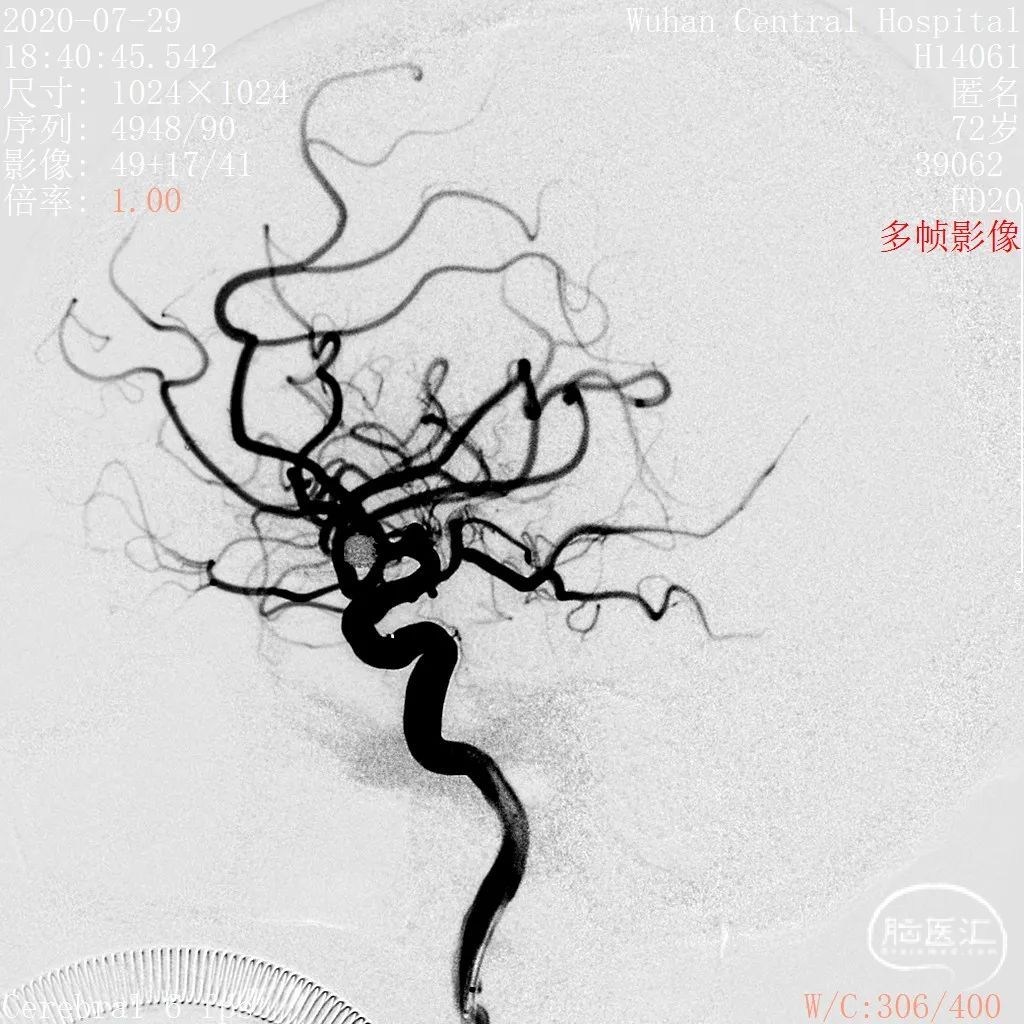

DSA结果:右侧大脑中动脉分叉部动脉瘤,约5.3*5.2mm,颈宽约2.9mm,形态囊状。

术前影像

DSA 2020-07-29